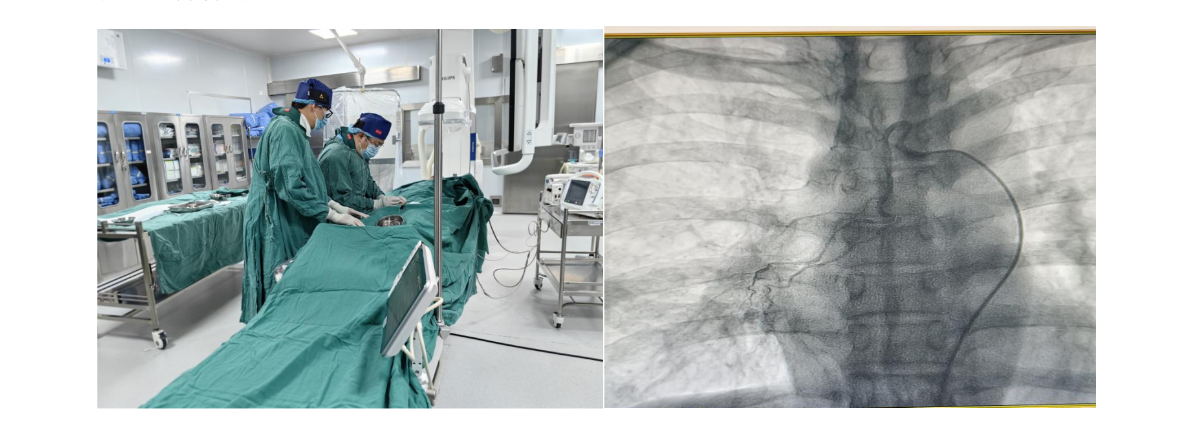

八、肺血管介入治疗

适应症:

1.肺癌患者无肺外转移,原则上应动脉内化疗或与栓塞同时进行。

2.肺结核、支气管扩张、原发性肺癌、肺脓肿、霉菌感染等致急性大咯血危及生命者或反复大量咯血经内科治疗无效者。

3.咯血经手术治疗复发者。